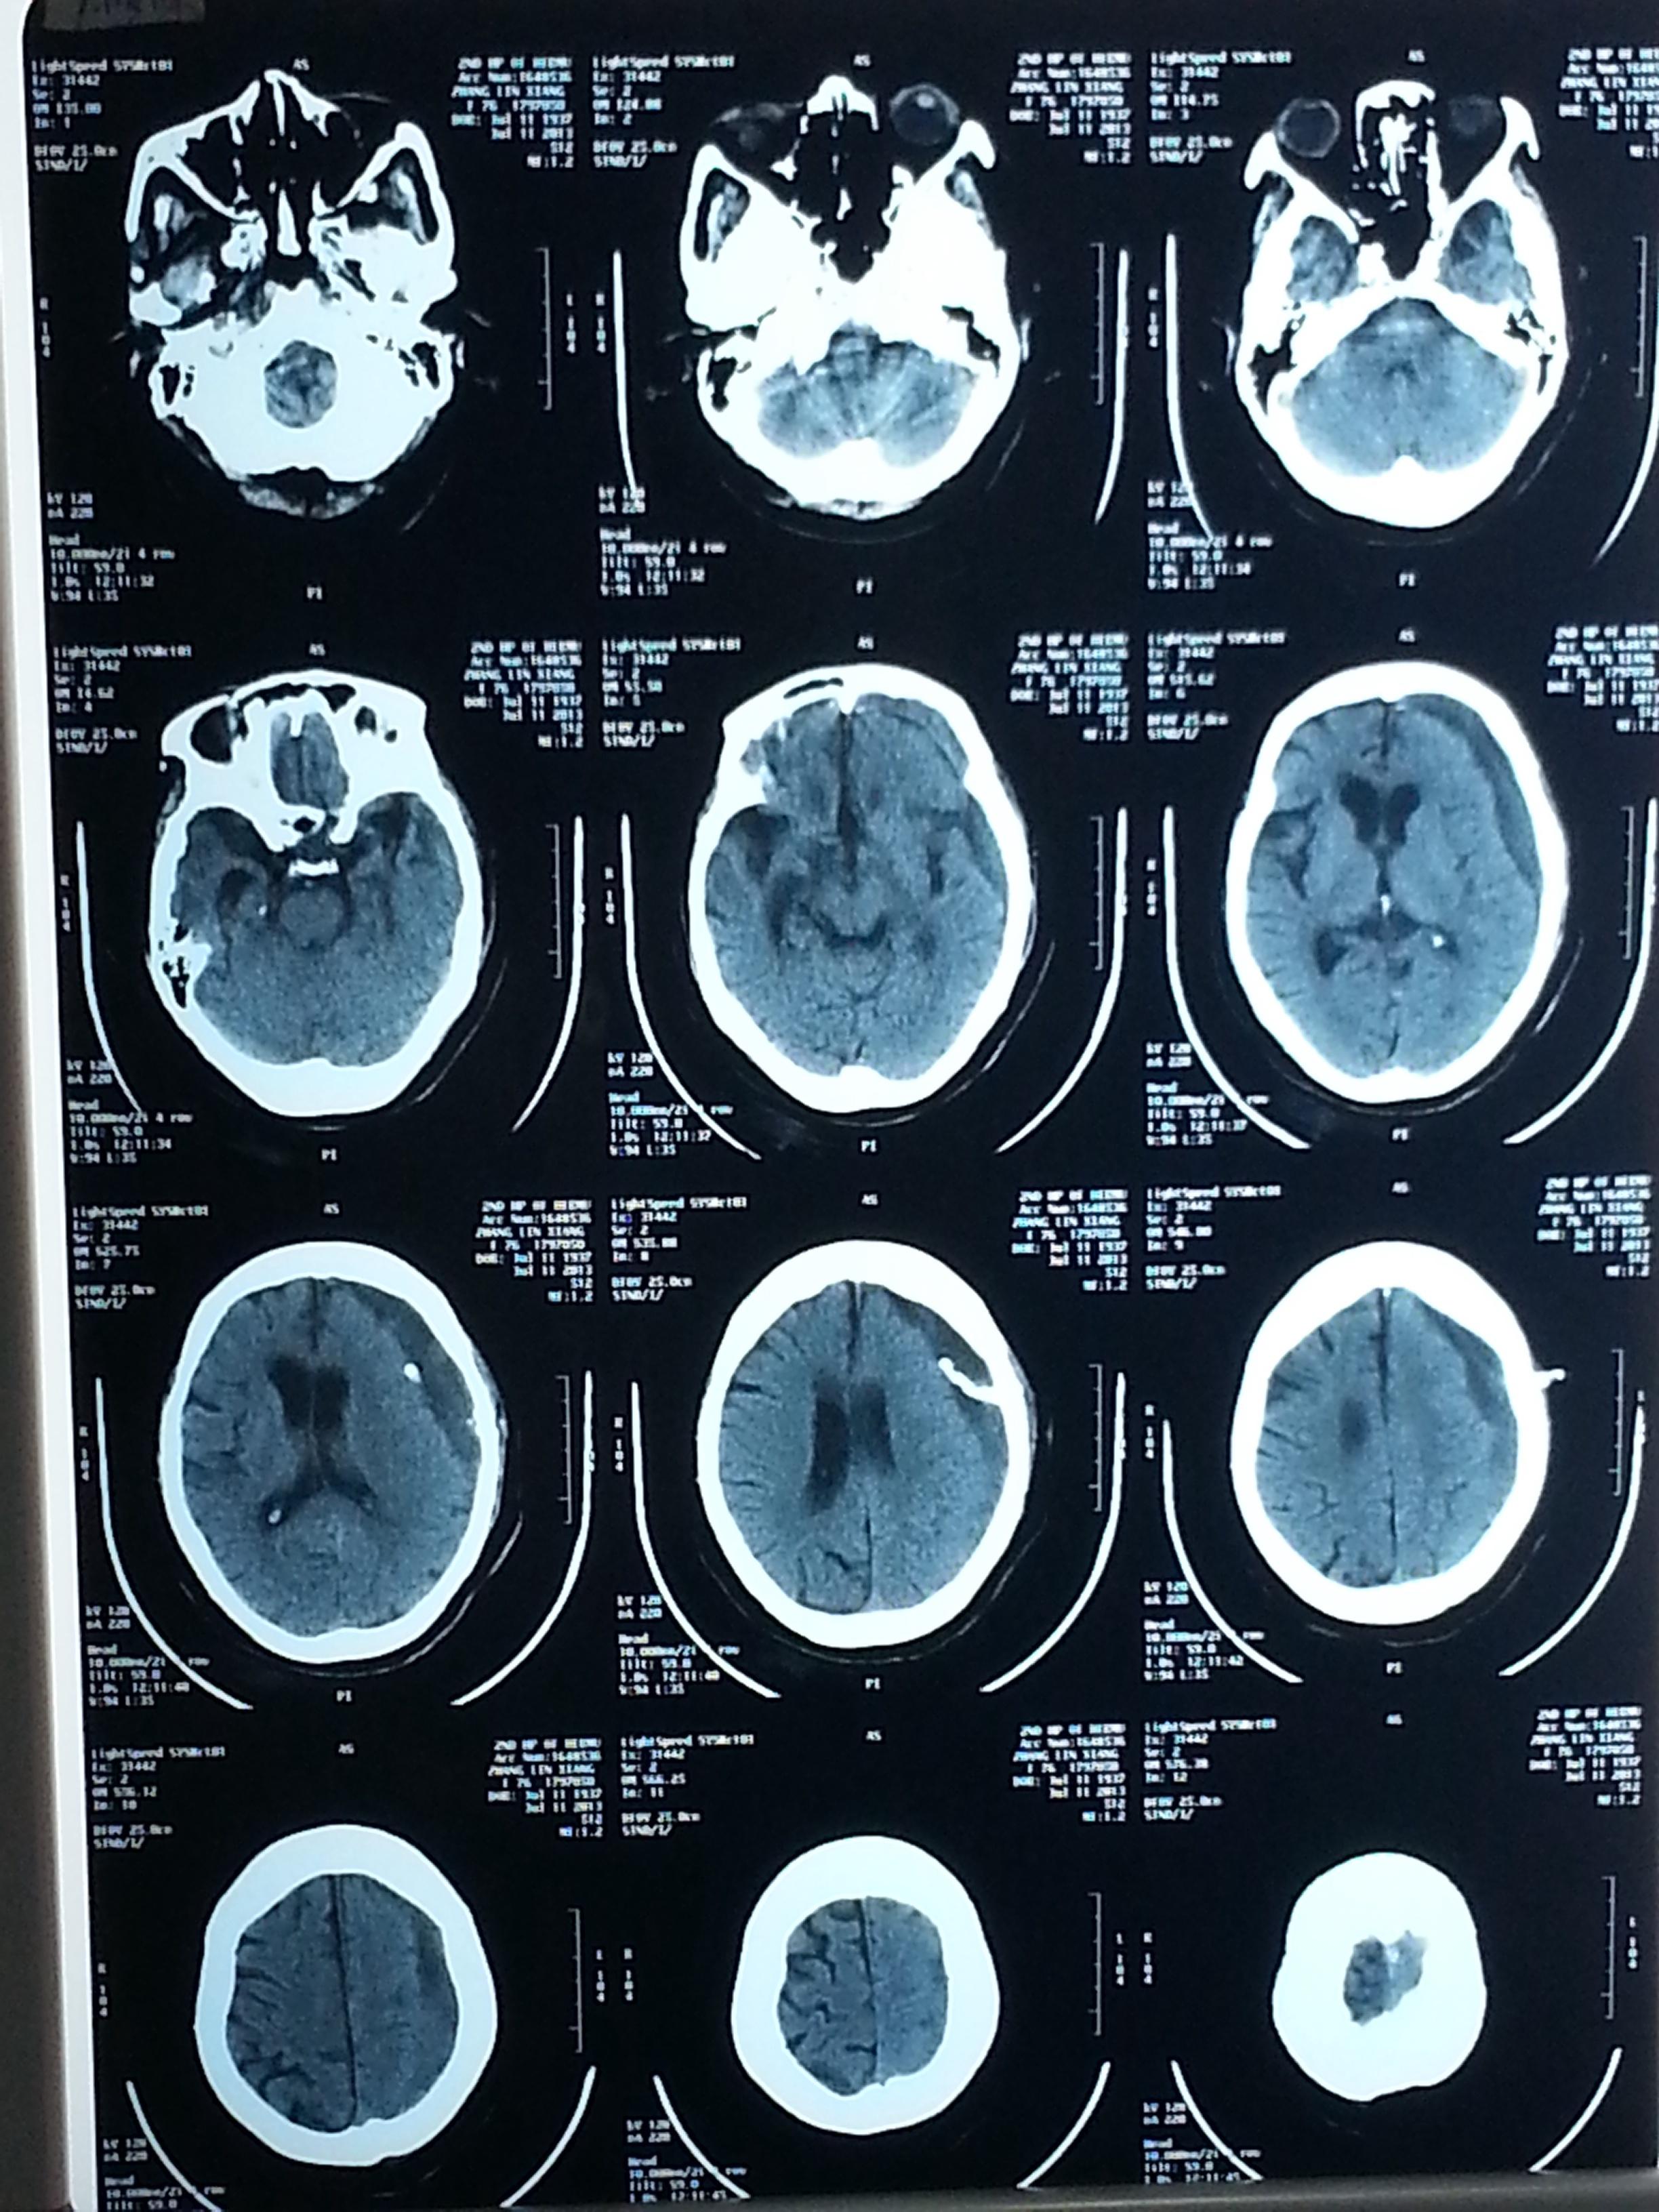

左侧硬膜下血肿并左枕叶脑出血,合并脑疝形成

急性硬膜下血肿

慢性硬膜下血肿